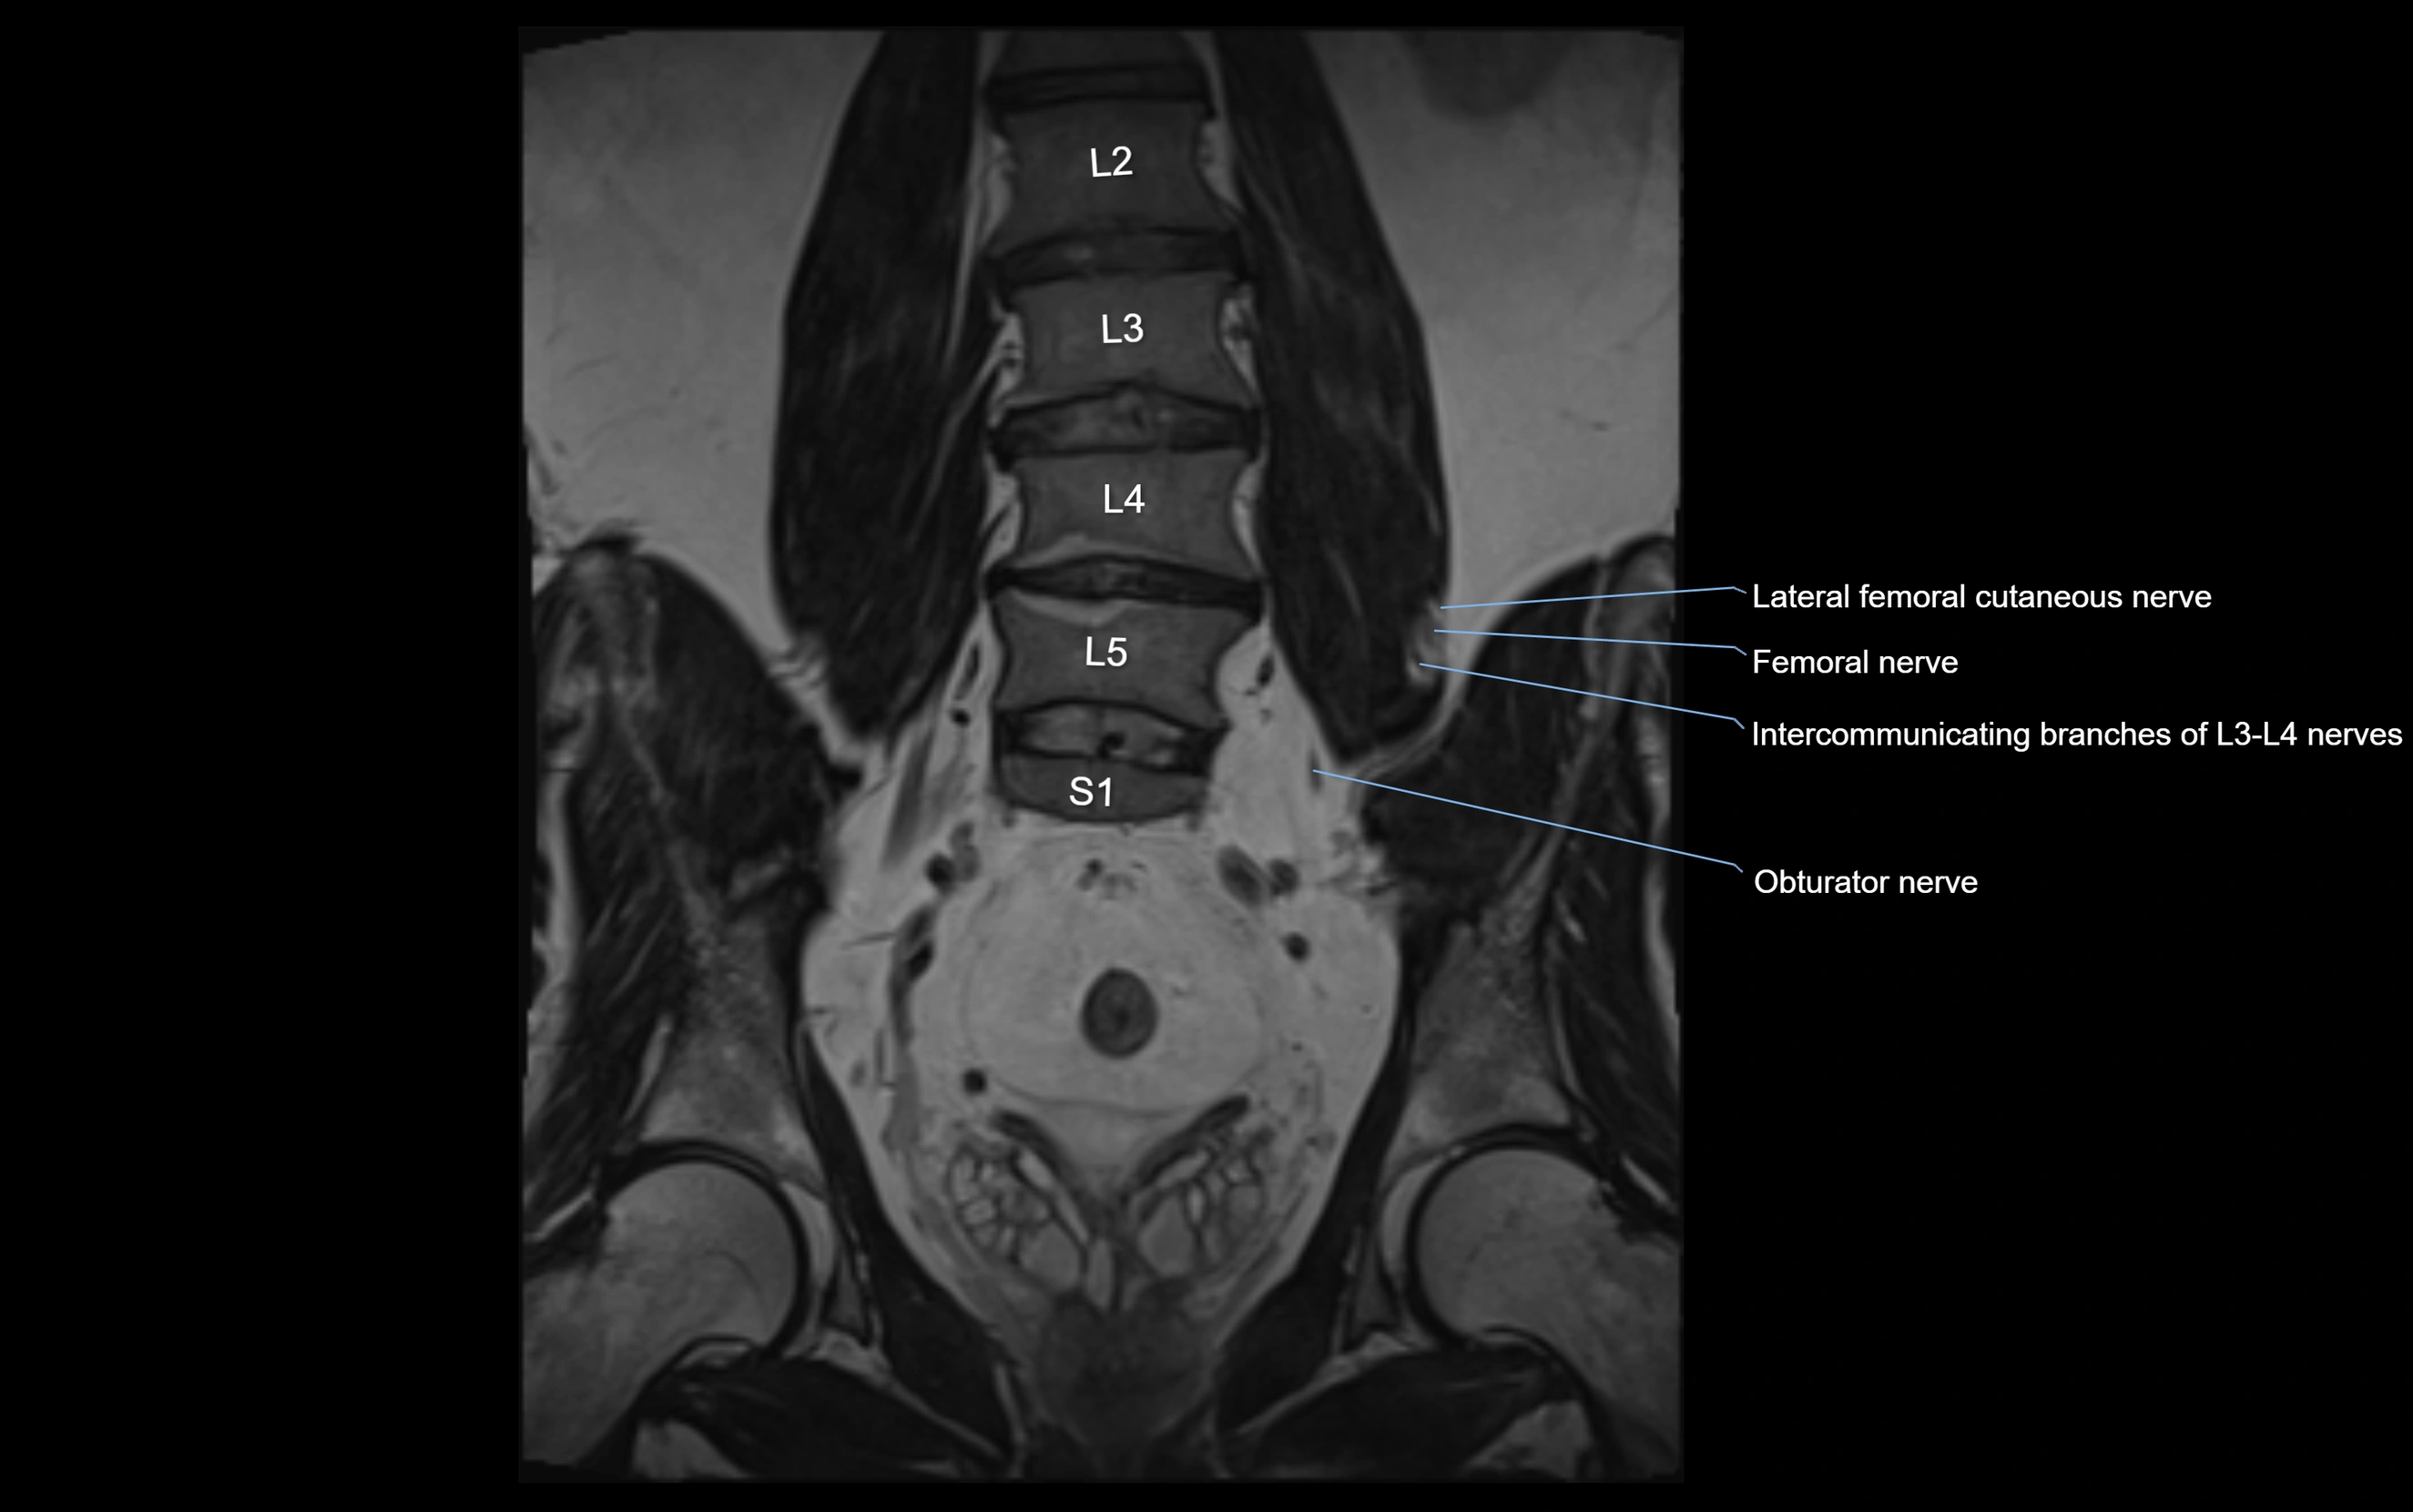

MRI image

image